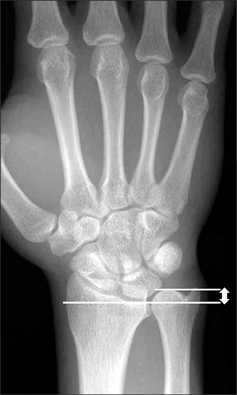

How is the load distribution in the wrist affected by ulnar variance?

What conditions are associated with the pathological finding of this XR? What would you expect to find on physical exam?

Ulnar Positive Variance

A pronated grip view is the best to determine your ulnar varience